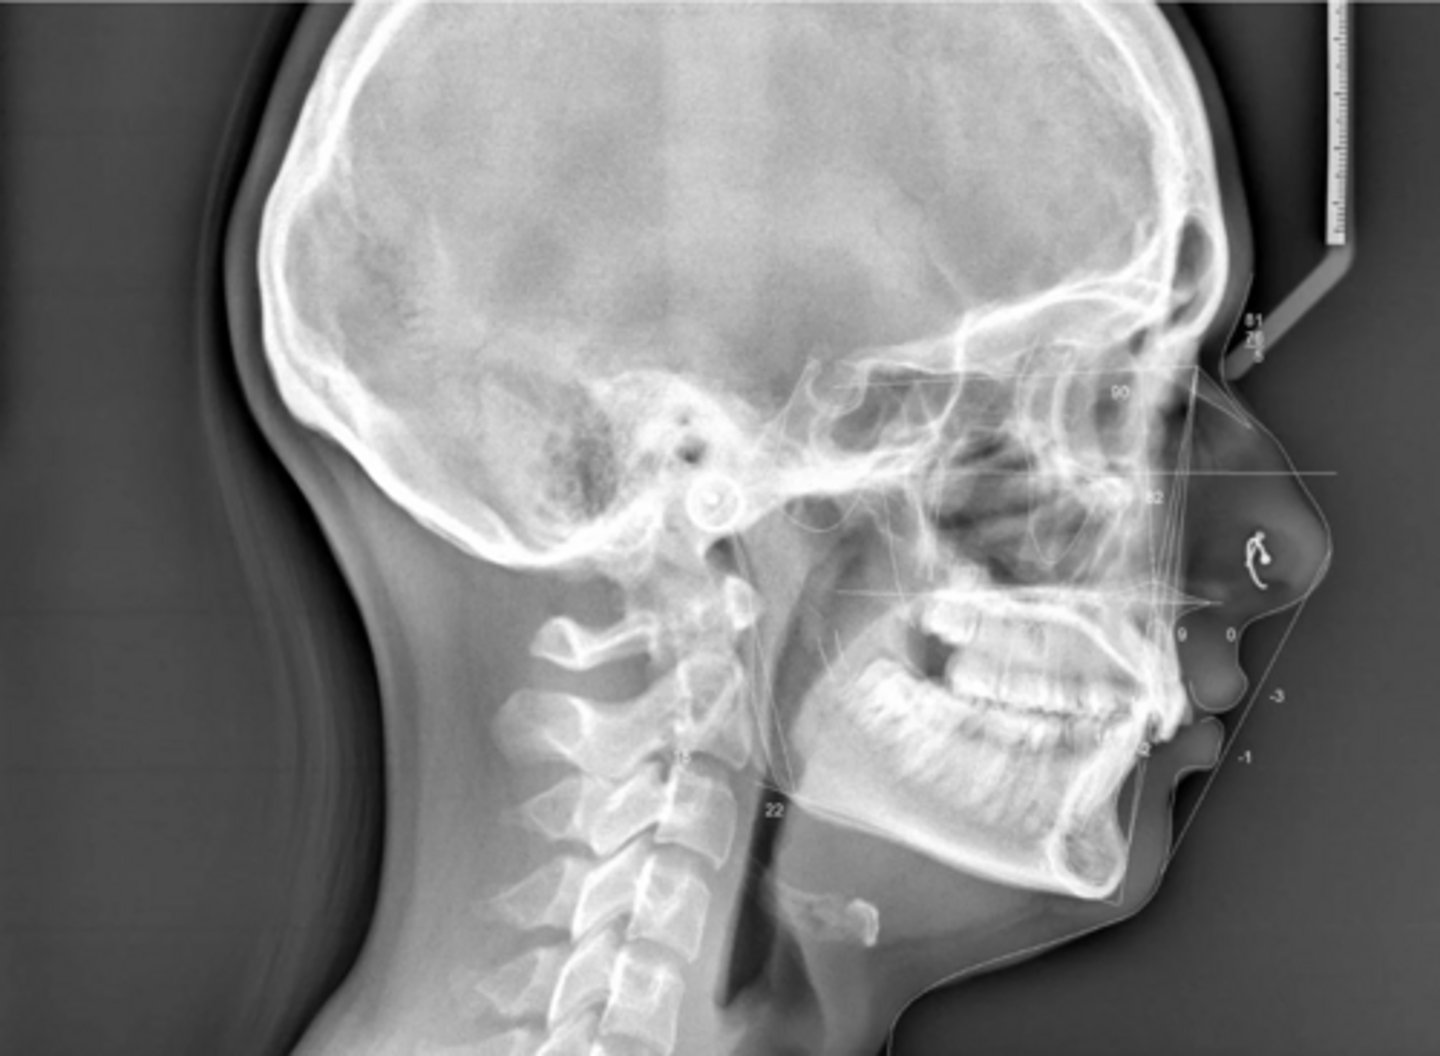

Class II

What type of skeletal malocclusion is this patient?

Hypodivergent

Are the hyper-, hypo-, o normo- divergent?

No

Are the maxillary incisors proclined/flared?